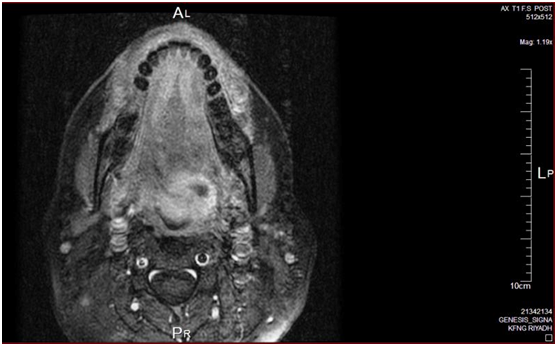

Endoscopy showed base of tongue mass, mainly in left side, smooth surface. Head and neck MRI showed moderately large mass 4×4×3cm seen in the left tonsillar\pyriform fossa regions pushing into the vallecula and extending through the tongue base posteriorly. PET CT showed prominent FDG focus localized to the BOT on the left side extending through hypopharynx on the left (SUV max 5.5) chest abdomen & pelvis was negative (Figure 1).

Figure 1 MRI T1 with contrast showing soft tissue mass on the left side of tongue base with irregular margins (2×3cm).